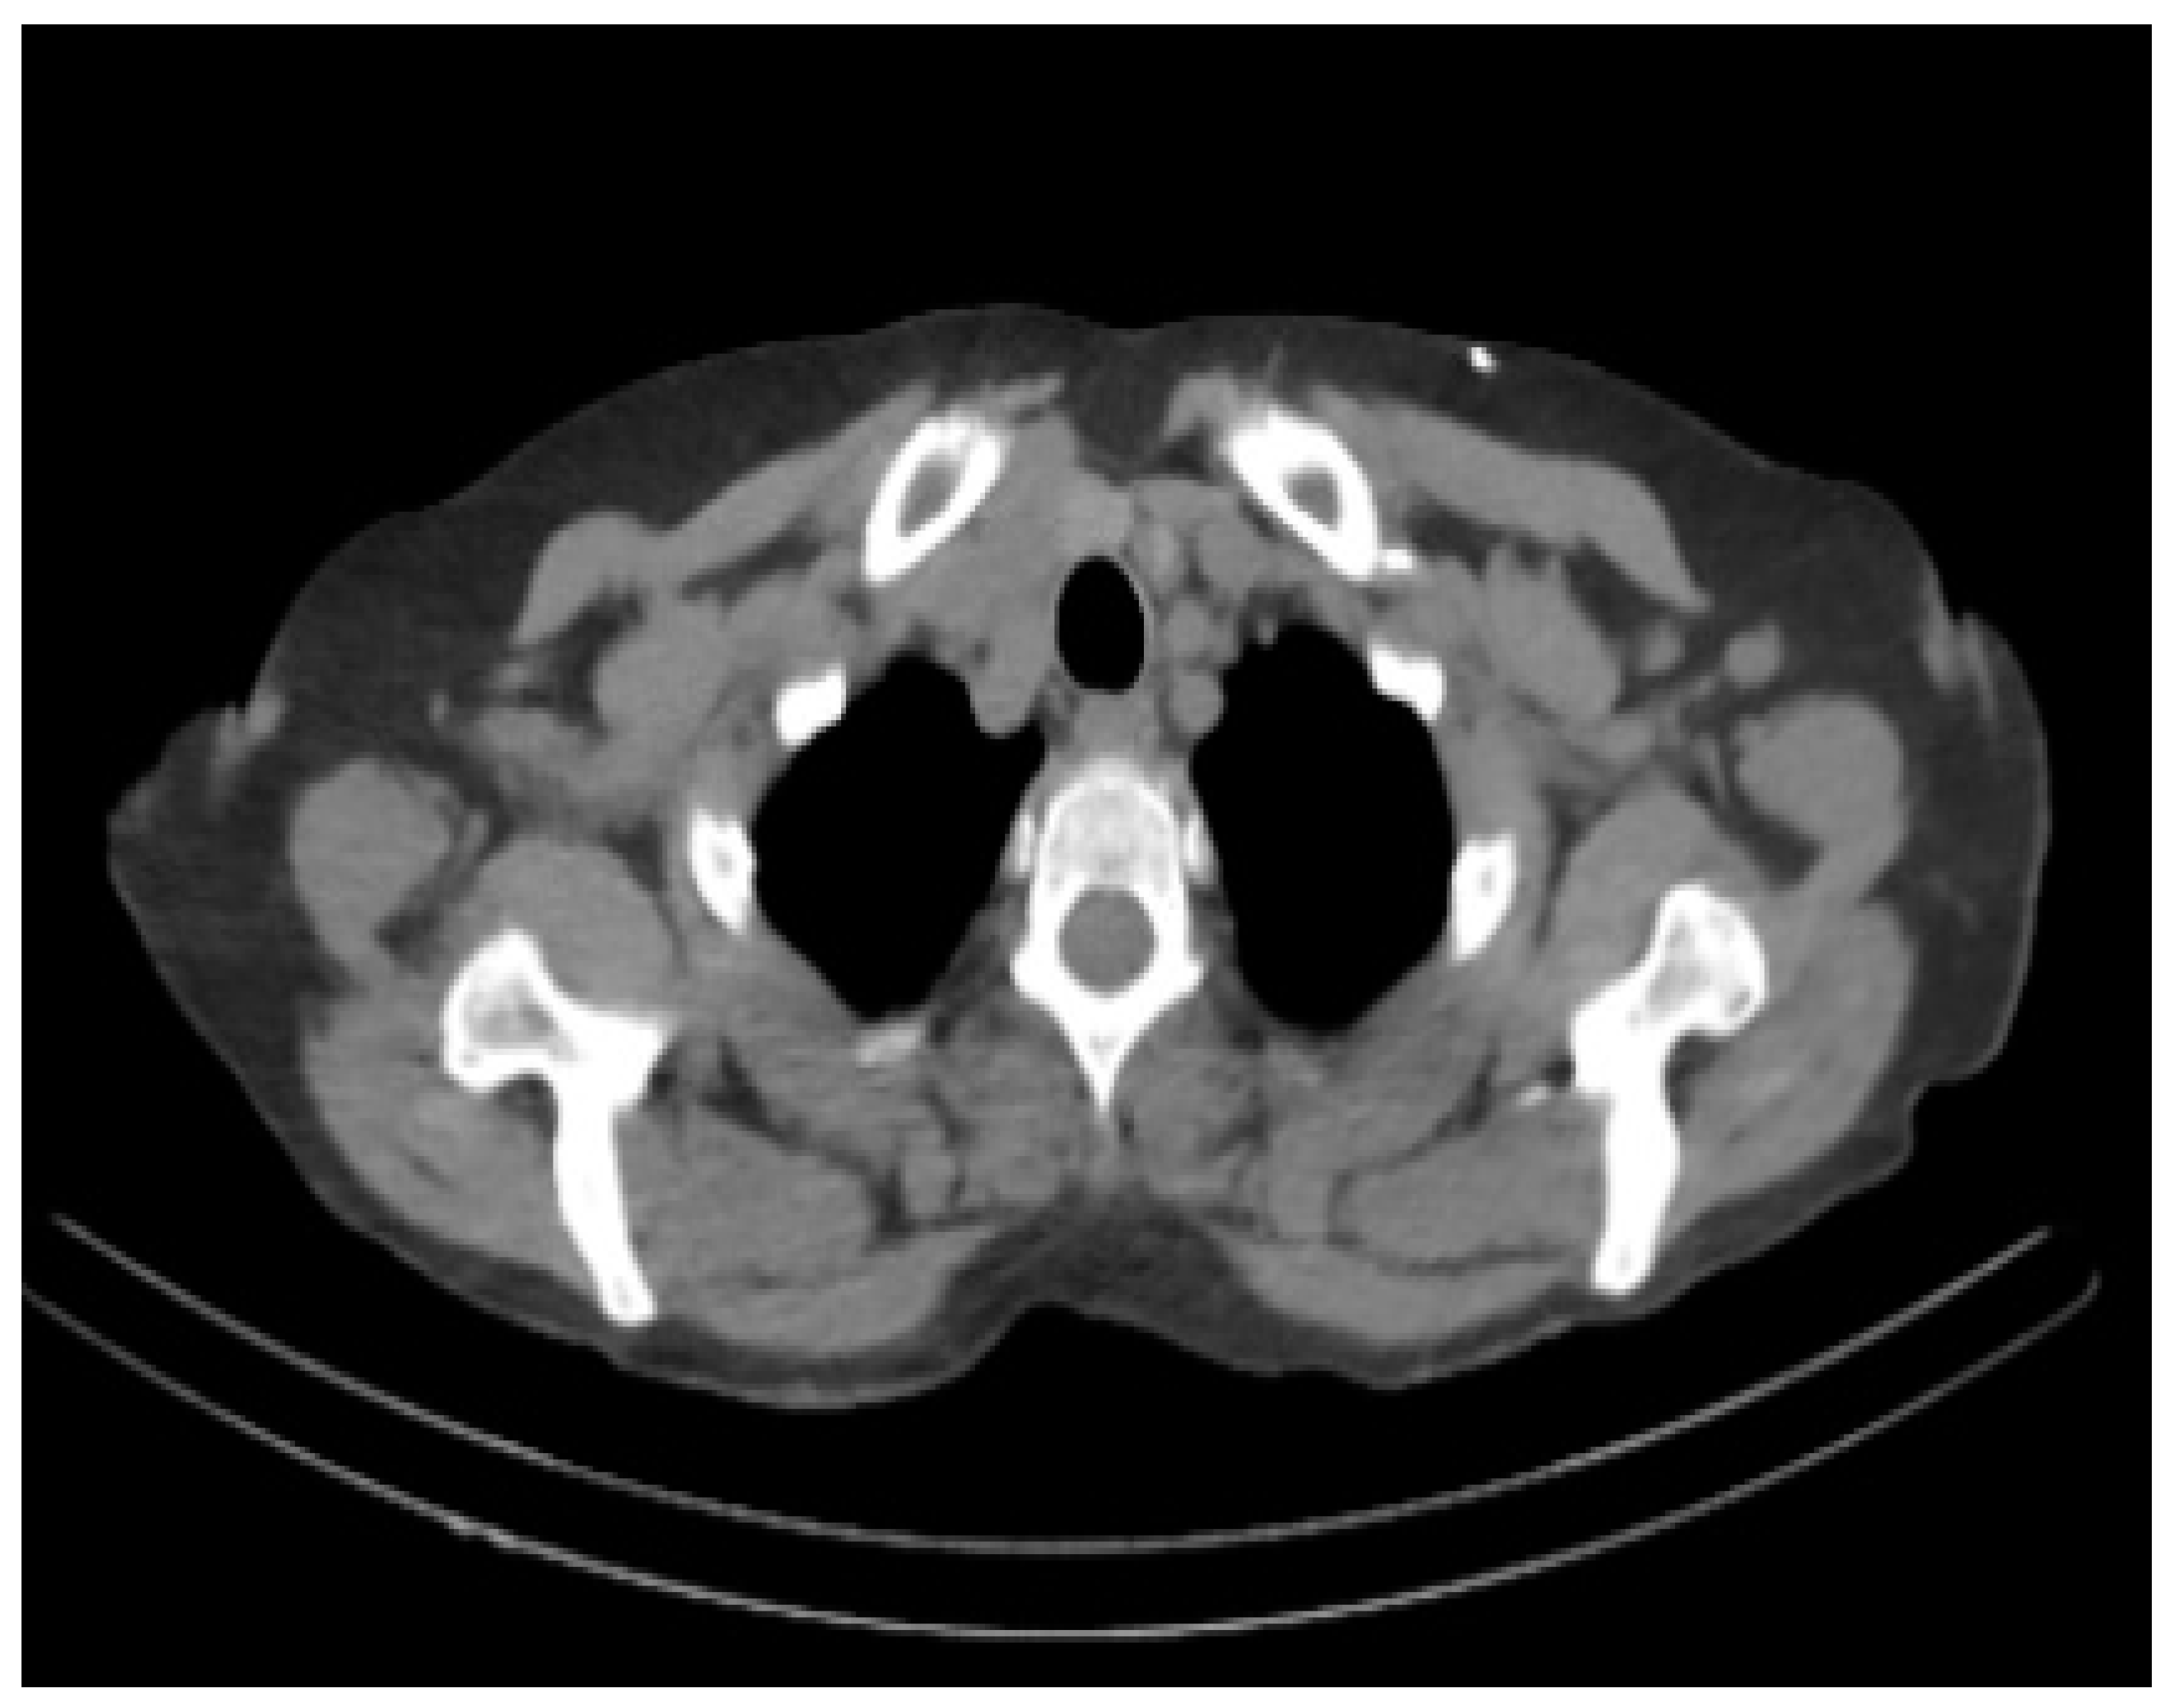

According to recent research, 1 in every 85 people might be impacted by AD by 2050 [3]. It is critical to detect and treat AD patients in their early stages. There are numerous methods available for identifying and predicting this dementia, including MRI, PET, and CT (Computed Tomography) scans, as shown in Figure 1; however, the most often used neuroimaging modality for diagnosing AD patients is MRI [4,5]. Earlier research studies have used MRI-based classification techniques with Machine and Deep Learning algorithms [6]. This paper aims to develop the finest prediction and detection methods possible with the assistance of radiologists, clinicians, and carers to save time and aid patients suffering from this condition [7,8].

Figure 1.

Healthy Brain vs. Alzheimer’s Diseased Brain. Compared to a healthy brain, the Alzheimer’s drain can be noted with shrinkage in size, less moisture, and enlarged ventricles.